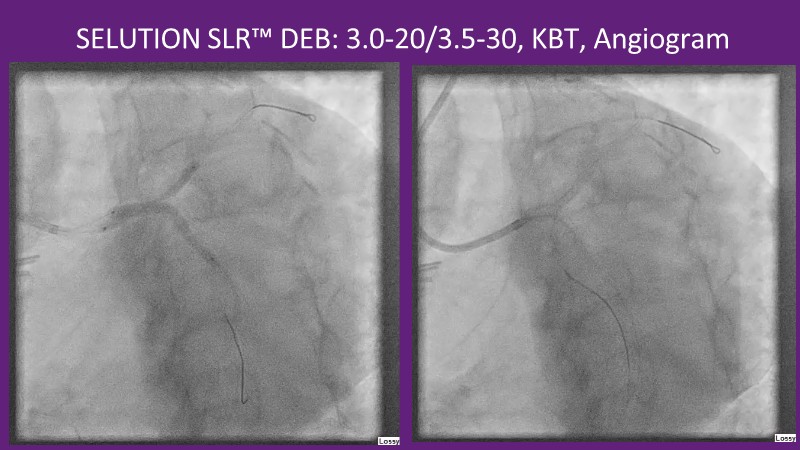

This EuroPCR 2025 session provides a comprehensive overview of drug-eluting balloons (DEBs) and their growing role in percutaneous coronary intervention (PCI). Gain a clear understanding of the clinical evidence and rationale supporting DEBs, including how these devices minimize metal implantation and effectively treat both standard and complex coronary lesions. The session highlights the mechanistic advantages of drug selection and sustained drug release technologies, with a focus on the SELUTION SLR DEB. Clinical updates include the LOVE-DEB study advocating a DEB-first approach in large vessel coronary artery disease, real-world performance data from the Malaysian registry, and practical case examples illustrating the transition to DEB-based PCI in clinical practice.